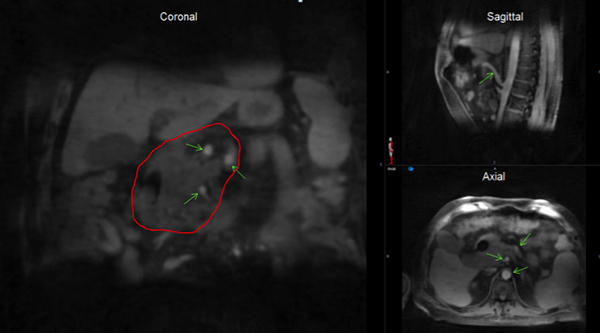

Novel 4-D-MRI images with high isotropic resolution, free from stitch artifacts and excellent blood vessel contrast that can be used to accurately define both pancreatic tumor and boost volume margins for SBRT with simultaneously integrated boost.

Implementing novel multi-parametric MRI for liver cancer patients showing excellent correlation of imaging-defined tumor and corresponding specimen cut. Functional MRIs resolved more heterogeneity within the tumor.